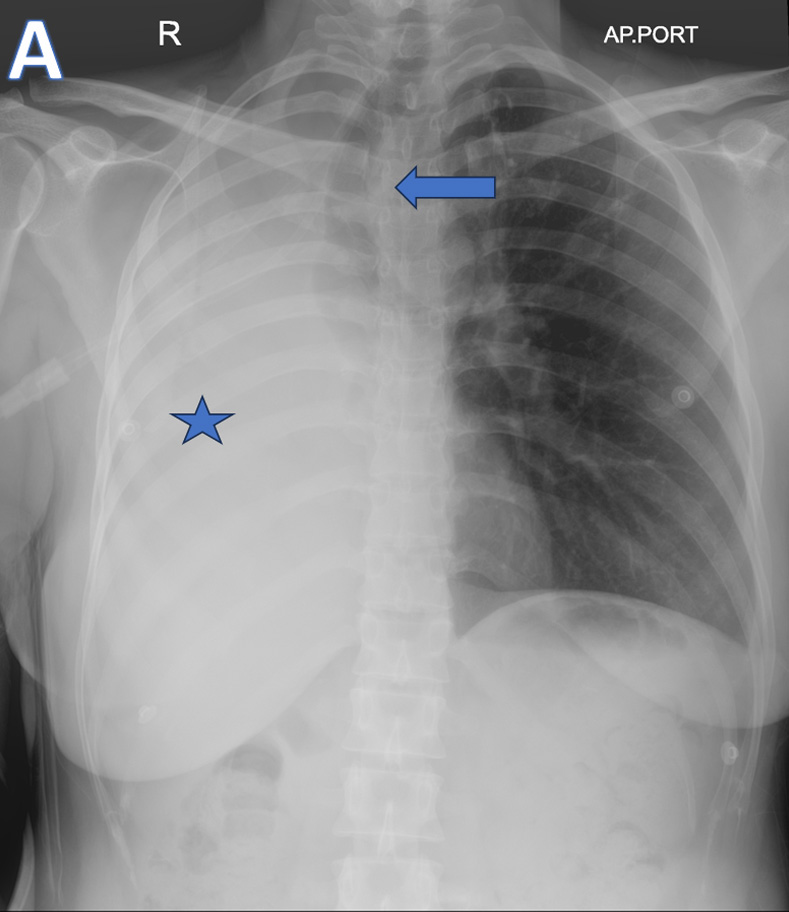

A - AP-Chest XRAY

• ARROW: Tracheal deviation to the Right.

• STAR: Opacified right hemithorax.

• Findings are consistent with Collapse of the right lung.